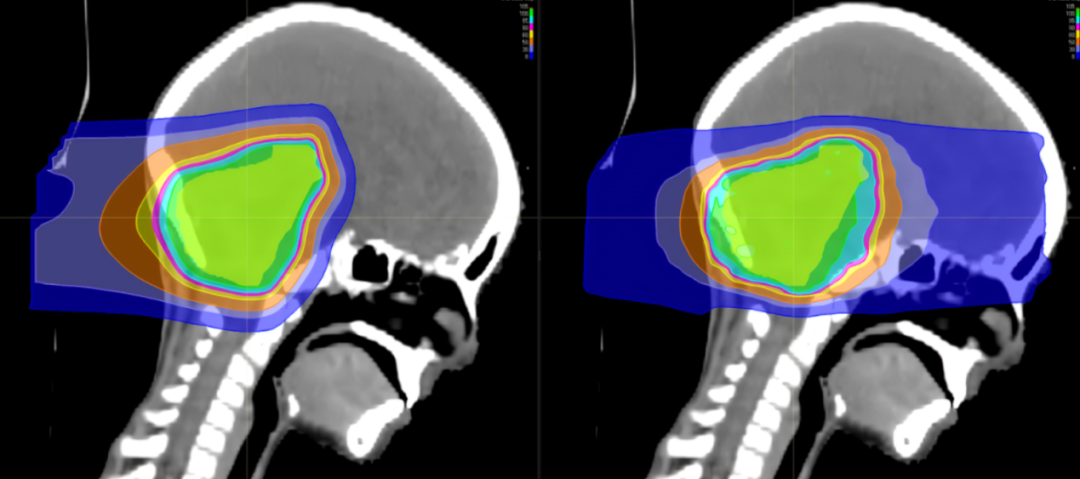

TOMO刀是一种基于层析成像技术的放射治疗系统,集CT断层扫描、肿瘤定位、360度螺旋适形、调强聚焦和照射于一体,可在CT引导下,根据肿瘤形态、大小,对各个射野内剂量分布进行调整,从而可以提供更精确的三维照射,减少对周围正常组织的伤害。TOMO刀在治疗肿瘤时可以调整放射束的强度和方向,使得治疗更加个性化和精准,同时减少了患者的不良反应。

射波刀是一种无创的放射外科手术技术,它利用高剂量的放射线聚焦于肿瘤组织,而对周围正常组织的伤害最小化。射波刀可以精确治疗脑部和颅内肿瘤、脑血管畸形,以及各部位常见恶性肿瘤,同时避免了传统手术可能带来的风险和并发症。(射波刀照射次数少,1-5次,单次放射剂量大,治疗周期短)